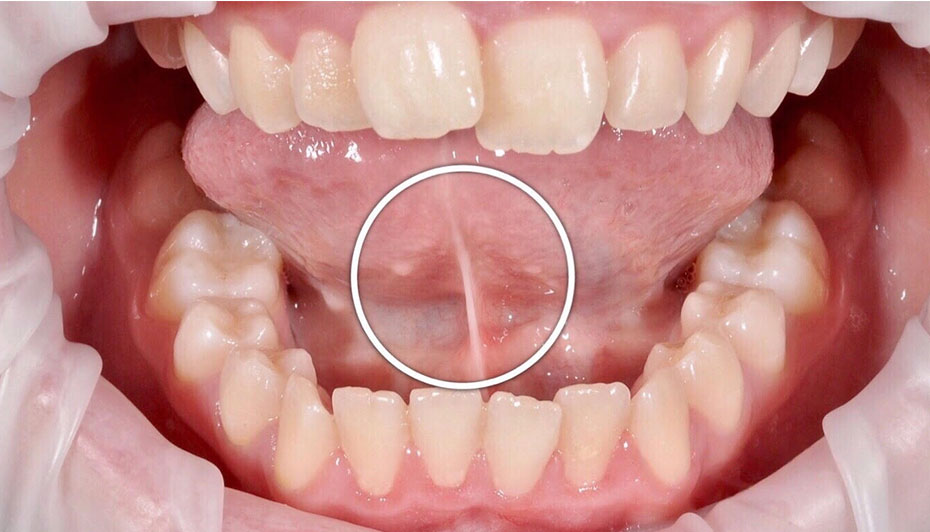

Tongue Tie Release

Tongue tie or ankyloglossia is a condition present at birth which restricts the tongue's range of motion It may interfere with breast-feeding in infants. In older children, it may cause unclear speech.

A simple surgery can be done to release the tongue tie. It must be followed by speech therapy to ensure best results.